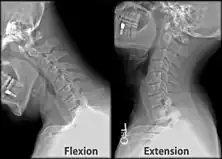

X-ray of cervical spine (neck) in flexion and extension (bending backwards)

Behind either condyle of the lateral parts of occipital bone is a depression, the condyloid fossa (or condylar fossa), which receives the posterior margin of the superior facet of the atlas when the head is bent backward; the floor of this fossa is sometimes perforated by the condyloid canal, through which an emissary vein passes from the transverse sinus.